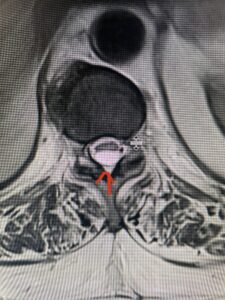

Fig. 2a Sagittal T2-weighted cervical MRI demonstrating large C4-5 herniated disc with spinal cord compression (red arrow)

Fig: 2b Axial T2-weighted cervical MRI demonstrating spinal cord compression from C4-5 herniated disc (red arrow)

This 47-year-old male who four months prior was lifting weights developed sharp pain in his neck. After that he developed progressive numbness in his arms, neck pain and headache. He said that the right arm was worse than the left. On examination the patient had long tract weakness on the right side which included his triceps, finger extensors, hip flexors, and dorsiflexors. The patient did not have hyperreflexia. MRI (Fig. 2) demonstrated a massive, extruded disc herniation with severe cord compression. The patient because of progressive myelopathy and spinal cord compression was indicated for anterior cervical discectomy and fusion at C4-5 (Fig. 3). Patient had significant improvement of weakness and numbness post operatively.